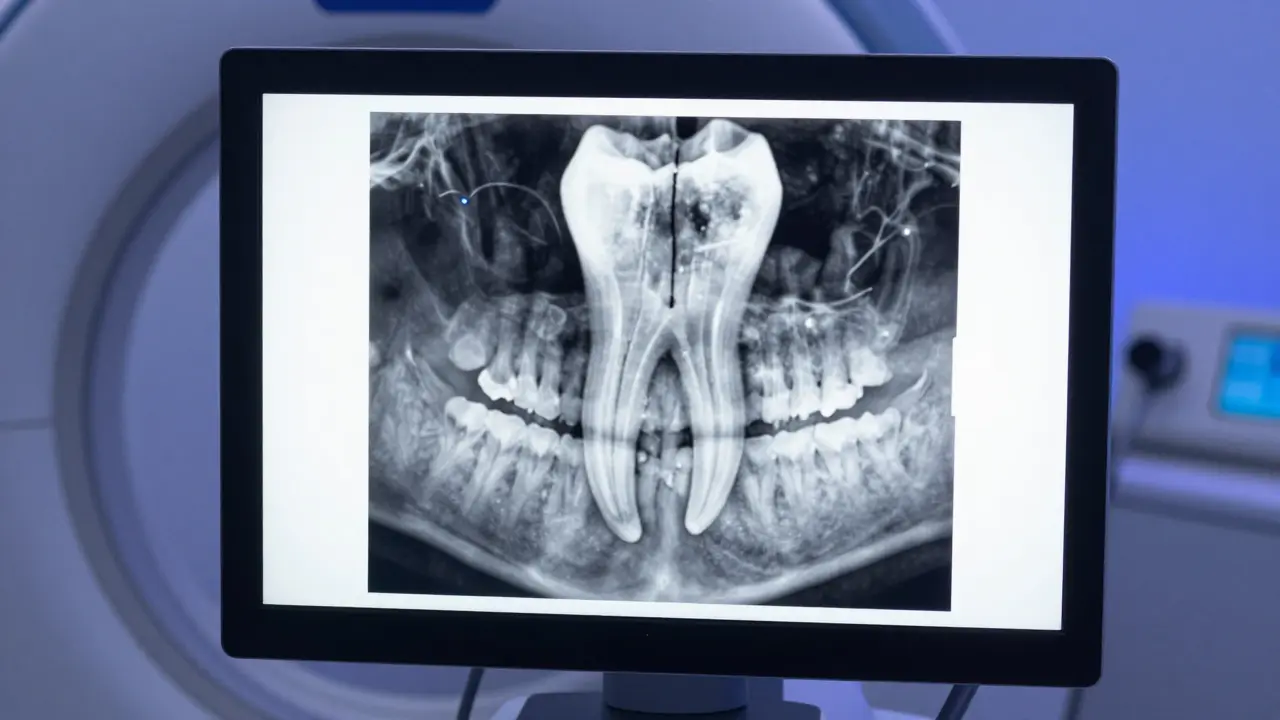

3D rentgenový snímek CBCT znázorňující prasklý kořen zubu na monitoru

Jak lékař diagnostikuje prasklinu, kterou není vidět?

Tady přichází ta nepříjemná část. Prasklina v kořeni je pro zubní lékaře noční můrou, protože standardní rentgen ji často nezachytí. Rentgen ukazuje 2D obraz, a pokud prasklina nevede přesně v rovině paprsků, zůstane neviditelná.

Moderní stomatologie proto používá CBCT, což je Cone Beam Computed Tomography, a 3D X-ray providing detailed views of dental structures. Díky 3D rekonstrukci lze vidět změny v kostním stěně kolem kořene, které jsou typické pro praskliny - často vypadají jako „jaloviny“ nebo vertikální stíny.

Lékař také využívá perkusi (poklepávání na zub) a sonduzování dásní. Pokud najde úzký oblastní hluboký vazyk v dásni, kde zub „vypadne“ při zkoumání sondou, je to velmi silný podezření na vertikální prasklinu. Někdy se používá i barvení prasklin speciálními laserovými barvy, které proniknou do štěrbiny a udělají ji viditelnou.